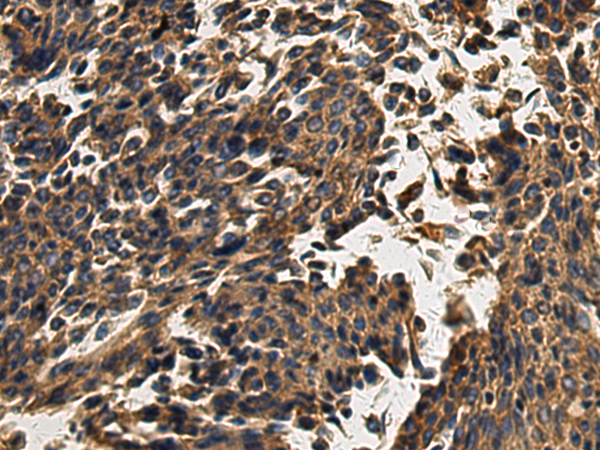

分类: 科研抗体货号: P10689别名: FLDB; LDLCQ4应用: IHC反应种属: Human, Mouse, Rat